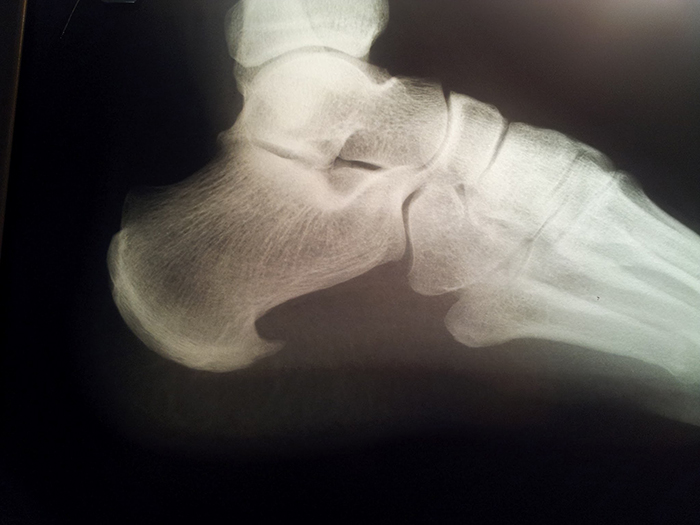

Espolón Calcáneo ó Fascitis Plantar

Es la inflamación crónica de la fascia plantar, una estructura que está en la planta del pie y que le confiere estabilidad. En algunos casos está asociada a la formación de una espícula ósea llamada espolón calcáneo.